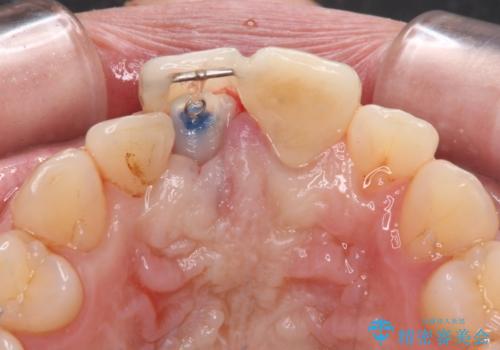

失活した歯は、根管治療を行った後に部分矯正により歯根を引っ張り出し、歯周外科処置により左右の歯肉の位置が揃えることとしました。

強い衝撃を受けた歯であるため、定期的にレントゲン撮影を行い、歯根吸収が起きていたり、神経が失活していたりしないか確認を行い、ある程度安定したところでオールセラミッククラウンにて補綴治療を行うこととしました。